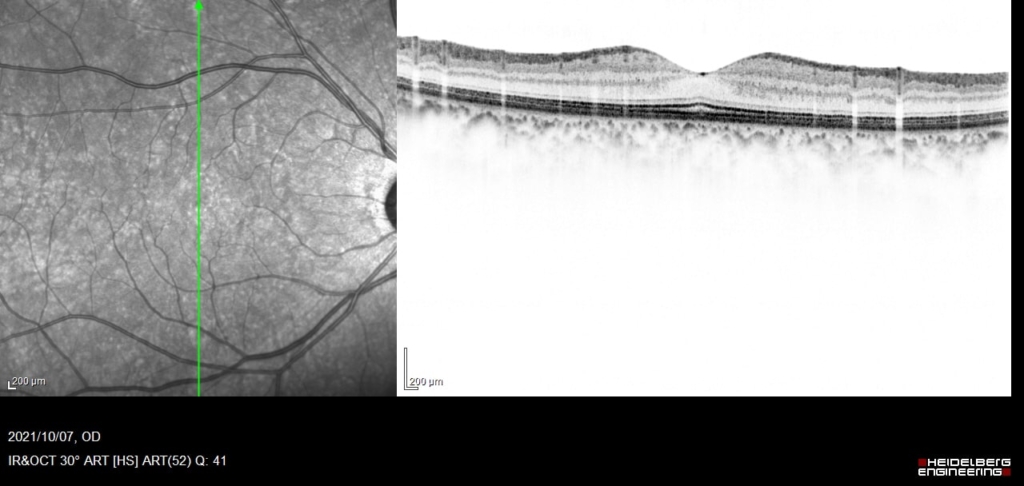

60歳 女性

主訴 10日前から飛蚊症、2日前から視野欠損を自覚

視力 右眼 0.6(1.2×-0.75)

鼻上側に剥離が剥離があり、格子状変性の耳側縁に馬蹄形裂孔がみられる。